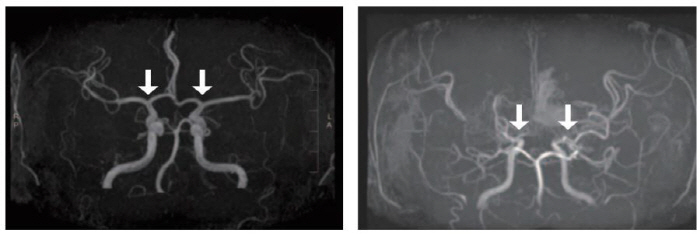

[스포츠조선 장종호 기자] 희귀질환인 소아 모야모야병 조기 진단 가능성을 높이는 새로운 바이오마커가 발견됐다. 모야모야병 환자의 뇌척수액에서 'SLITRK1' 단백질 발현이 유의미하게 높은 것으로 나타났다. 또한 뇌경색, 수술 예후 등 모야모야병의 임상 특성과 연관된 단백질도 확인돼, 난치성 질환인 모야모야병 치료에 새로운 패러다임을 제시할 것으로 기대된다.

연구팀은 모야모야병 환자군(104명)과 대조군(14명)의 뇌척수액 내 단백체를 포괄적으로 분석했다. 그 결과 총 2400여개의 단백질이 확인됐으며, 그중 8개가 환자군에서 상대적으로 발현 강도가 높았다. 이 단백질들을 대상으로 한 효소면역분석에서 특히 신경세포 성장과 연관된 'SLITRK1'의 농도가 높게 나타났다. 이는 신경세포가 모야모야병 진행 기전에 영향을 줄 수 있음을 시사한다.

추가적으로 연구팀은 가중 유전자 공발현 네트워크 분석을 통해 변화 패턴이 유사한 단백질들을 그룹화하고, 모야모야병 임상 특성과의 연관성을 규명했다. 그 결과, 수술 전 뇌경색 발생 환자는 BASP1, LDH 발현이 높았고, 좋은 수술 예후를 보인 환자는 CD9, EMILIN1 발현이 높은 것으로 나타났다. 특히 신생 혈관 형성을 촉진하는 CD9 발현이 높을수록 mRS 점수(수술 후 기능 장애 정도)가 낮아져, 이 단백질과 모야모야병 수술 예후의 연관성이 확인됐다.

서울대병원 김승기 교수(소아신경외과)는 "이번 연구를 통해 뇌척수액에서 소아 모야모야병의 조기 진단과 치료를 위한 바이오마커를 발견하고, 효율적인 액체 생검 기반 진단법 개발에 한 걸음 다가섰다"며 "특히 새롭게 규명된 모야모야명 예후 예측 지표는 맞춤형 치료 전략 수립의 토대가 될 수 있을 것"이라고 말했다.